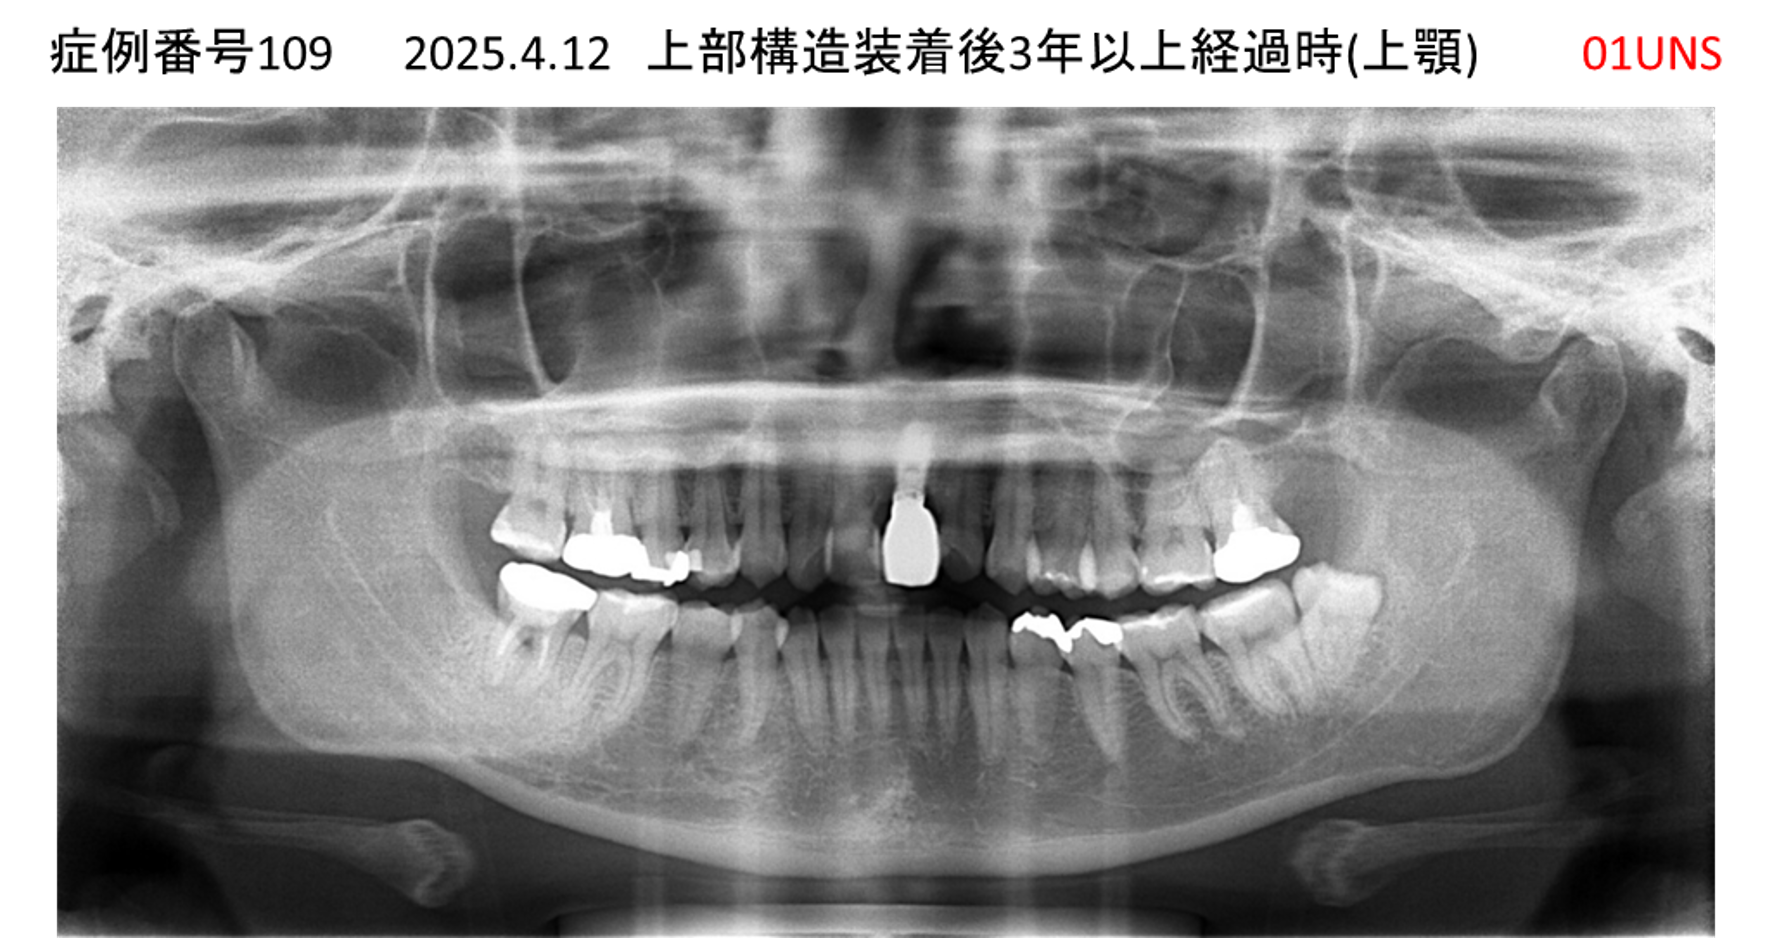

上の前歯がおかしな方向になった患者様のインプラント症例

| 治療名称 |

インプラント |

| 治療費用 |

235万円+税 |

| 治療期間 |

5か月 |

| 患者さんの症状(主訴) |

上の前歯がおかしな方向になった。全く噛めず、最近は食事もまるのみ状態。 |

| 治療内容 |

サイナスリフト インプラント |

| 治療結果 |

見た目がとても良くなった。ご飯が何でも食べることがうれしい。 |

| 治療の注意点(リスク/副作用) |

インプラントが壊れたら再治療が必要 |